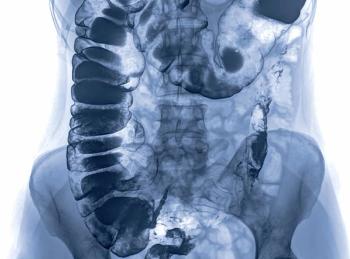

Phase 2/3 Study of Circulating Tumor DNA as a Predictive Biomarker in Adjuvant Chemotherapy in Patients With Stage IIA Colon Cancer (COBRA): a first-in-kind trial seeks to provide level 1 evidence in evaluating the role of ctDNA as a guide for clinicians in the decision to administer adjuvant chemotherapy to patients with stage IIA colon cancer (NRG GI-005) (NCT04068103).

Colon Adjuvant Chemotherapy Based on Evaluation of Residual Disease (CIRCULATE-US): a prospective phase 2/3 trial of MRD-based adjuvant therapy for patients with early-stage colon cancer with intensified and deintensified adjuvant therapy approaches using ctDNA status as a surrogate for MRD status (NRG-GI008) (NCT05174169).

Ibrahim Halil Sahin, MD, and colleagues, explore, the CIRCULATE-US (NRG-GI008; NCT05174169) investigating postoperative ctDNA dynamics in early-stage colon cancer for treatment selection.

Ben Fangman, MD, and colleagues provide an overview of the use of circulating tumor DNA levels to detect minimal residual disease in colorectal cancer.

Co-editor-in-Chief Howard S. Hochster, MD, highlights exciting clinical trials that may set future standards for adjuvant therapy selection in colon cancer.